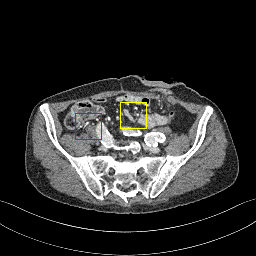

Figure 6: Visual comparison of SRCT Case 222 from the abdominal dataset. The display window is [-160, 240] HU. The restored anatomical features are shown in the red and yellow boxes. (Zoomed for visual clarity).

III-E Experimental Results on the Abdominal Dataset

We further compared the above-mentioned algorithms on the abdominal benchmark dataset. A similar trend can be observed on this dataset. Our proposed GAN-CIRCLE can preserve better anatomical informations and more clearly visualize the portal vein as shown in Fig. 6. These results demonstrate that PSNR-oriented methods (FSRCNN, ESPCN, LapSRN) can significantly suppress the noise and artifacts. However, it suffers from low image quality as judged by the human observer since it assumes that the impact of noise is independent of local image features, while the sensitivity of the Human Visual System (HVS) to noise depends on local contrast, intensity and structural variations. Fig. 6 displays the LRCT images processed by GAN-based methods (SRGAN, G-Adv, GAN-CIRCLE, GAN-CIRCLEs, and GAN-CIRCLEu) with improved structural identification. It can also observed that the GAN-based models also introduce strong noise into results. For example, there exist tiny artifacts on the results of GAN-CIRCLEu. As the SR results shown in Fig. 6, our proposed approaches (GAN-CIRCLE, GAN-CIRCLEs) are capable of retaining high-frequency details to reconstruct more realistic images with relatively lower noise compared with the other GAN-based methods (G-Adv, SRGAN). Table II show that G-Fwd achieves the best performance in PSNR. Our proposed methods GAN-CIRCLE and GAN-CIRCLEs both obtain the pleasing results in terms of SSIM and IFC. In other words, the results show that the proposed GAN-CIRCLE and GAN-CIRCLEs generate more visually pleasant results with sharper edges on the abdominal dataset than the competing state-of-the-art methods.